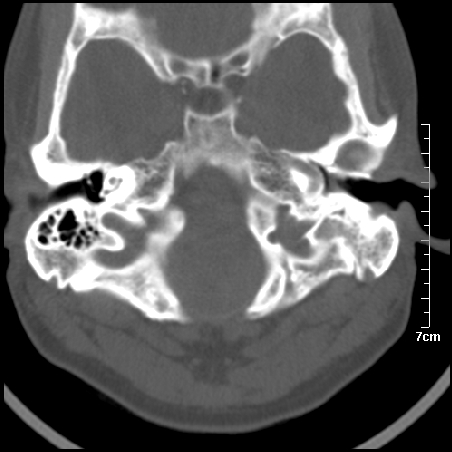

病例2

m/27

胆脂瘤是是以鳞状上皮内衬充满角质化碎片的囊,随着角化屑片的不断堆积,肿块逐渐增大,胆脂瘤可为先天性(2%)或后天性(98%)。胆脂瘤有感染史。中耳内的鳞状上皮通常有外耳道的上皮通过一鼓膜的缺损移行至中耳,其他的原因包括鳞状上皮化生。由于欧氏管的功能不全所引起的中耳负压可产生上鼓室鼓膜松弛部的牵引性开袋。继而发展成胆脂瘤。成年人胆脂瘤时乳突常发育差,而儿童常有广泛性乳突气化,这种气化可导致胆脂瘤的更广泛的乳突扩散。后天性胆脂瘤患者大多数存在骨质破坏。

松弛部胆脂瘤有中央性穿孔或后上部牵引口袋所致。紧张部胆脂瘤经常侵蚀听小骨并引起传导性耳聋。

中耳胆脂瘤有两个重要并发症:一是面神经管的水平段受暴露,二是外侧半规管受侵蚀产生瘘管。面神经在ct上难以显示或不可能显示,除非其周围有空气包绕或有良好轮廓的骨性覆盖。胆脂瘤还可合并感染,产生于急性中耳炎.乳突炎所描述的那些合并症。